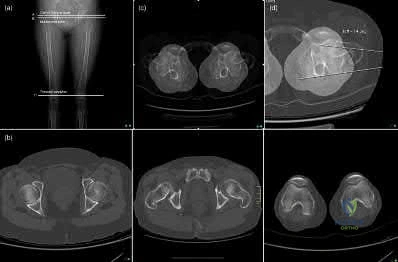

Figure A demonstrates a bicondylar tibial plateau fracture. Figure B demonstrates fixation of a tibial plateau fracture through a dual plating technique.

A 37-year-old male sustained the injury shown in figure A. He was treated with an intramedurally nail and a post-operative radiograph is shown in figure B. He underwent a post-operative CT Scanogram to assess for rotation. Figures C and D are of the operative side and Figures E and F are of the uninjured side. What is the version of the injured side and should any further procedures be undertaken for correction?

Figure A demonstrates a subtrochanteric femur fracture, while Figure B demonstrates the same fracture, stabilized with a piriformis entry nail. Figures C-F demonstrate axial CT cuts to determine femoral version. Figure C demonstrates hip anteversion of 18 degrees, while figure D reveals knee external rotation of 18 degrees. This side exhibits neutral rotation (18-18).

Figure E demonstrates hip anteversion of 9.2 degrees while figure F demonstrates knee external rotation of 3.2 degrees. This side exhibits 6 degrees of anteversion (9.2-3.2).